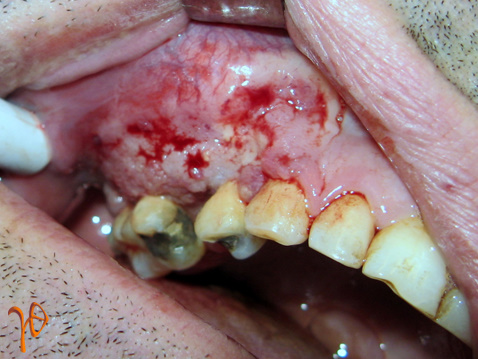

Στην κλινική εξέταση, ο ασθενής εξωστοματικά εμφάνιζε σκληρή ανώδυνη διόγκωση της παρειάς με εξάλειψη της ρινοχειλικής αύλακας(Εικ. 3) και ενδοστοματικά έφερε ανώδυνη συμπαγή και μαλακή μάζα με κοκκιώδη επιφάνεια η οποία καταλάμβανε τα ούλα και την ουλοπαρειακή αύλακα από την περιοχή του κυνόδοντα μέχρι και τον δεύτερο γομφίο(Εικ. 4).

Εικόνα 4. Βλάβη των ούλων εκτεινόμενη στην ουλοπαρειακή αύλακα.